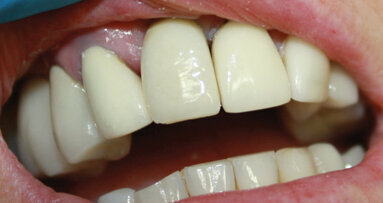

A 24-year-old female patient in excellent medical and good dental health presented stating she had not been to the dentist in some time and wished to improve her oral health and the appearance of her teeth. The pa­tient was unhappy with the shape and shade of her teeth. She was particularly concerned with the im­proper proportions of the width-to-length ratios of her incisors and the diastema present between teeth #11 and 21 (Figs. 1 & 2).4 Several areas of gingival asymmetry were also noted. The patient stated that she had re­ceived orthodontic treatment in the past, and cos­metic bonding (which had already failed at the time of her presentation) to close the diastema between teeth #11 and 21. She expressed her desire to have a beautiful, brighter and natural-looking smile.

Fig. 1: Pre-op full smile.

Fig. 2: Pre-op retracted view showing the diastema and improper proportions of the width-to-length ratios.